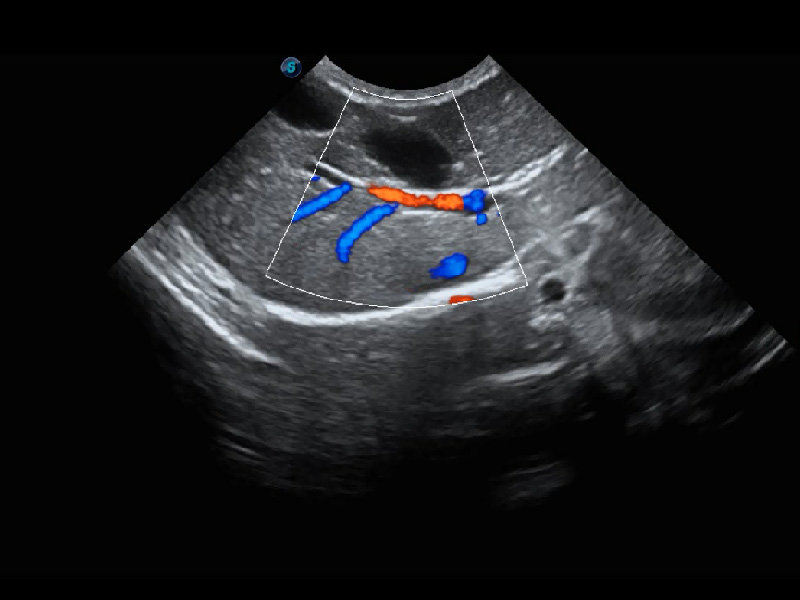

(犬)四腔心血流